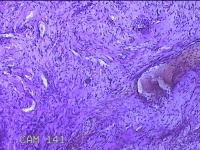

舌头肿物

性别

女

年龄

25岁

临床诊断

一般病史

无

标本名称

大体所见

灰白粉红色肿物0.7x0.5x0.2cm一个,表面光滑。

纤维性息肉